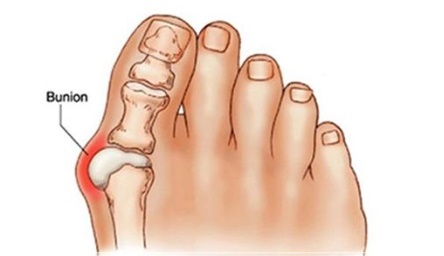

무지외반증은 엄지발가락이 둘째발가락 쪽으로 심하게 휘어져 엄지발가락 관절이 안쪽으로 돌출된 상태를 말하며, 심한 경우에는 엄지발가락이 둘째발가락과 엇갈리는 정도까지 돌아가기도 합니다. 특히 앞이 좁고 굽이 높은 신발을 자주 신는 여성에 흔한 대표적인 족부 질환입니다.

엄지 발가락의 튀어나온 관절부분(건막류)이 신발에 눌려 통증을 호소하는 것이 주 증상이나 엄지발가락이 둘째발가락 쪽으로 휘어져 있고, 관절이 안쪽으로 돌출되어 있습니다. 돌출된 관절은 서 있거나 걸을 때 자극을 받아 빨갛게 변하고 굳은살이 잡히며 염증과 통증이 발생합니다. 엄지발가락이 제 역할을 하지 못하니 발의 다른 부위에도 통증이 생기고 심해지면 발 모양의 변형, 허리의 통증 등이 발생합니다.